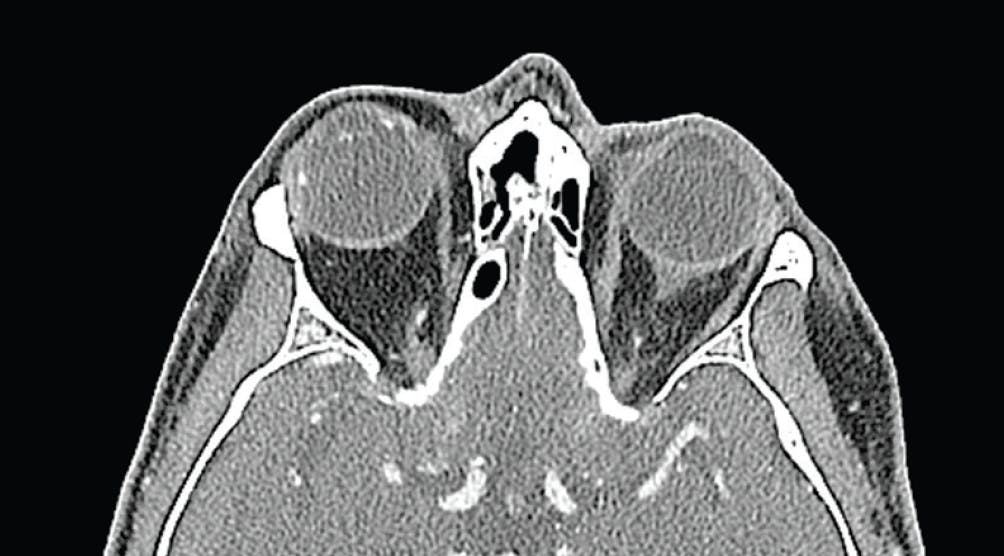

Fundoscopic examination of the right eye showed an attached retina supported on a scleral buckle without evidence of intrusion. The left eye was unremarkable. A CT scan of the orbits revealed the implanted scleral buckle with a somewhat diagonal orientation in the axial plane, but no evidence of pre- or post-septal cellulitis (Figure 2).

Figure 2. The CT scan revealed the implanted scleral buckle with a somewhat diagonal orientation in the axial plane, but no evidence of associated pre- or post-septal cellulitis.